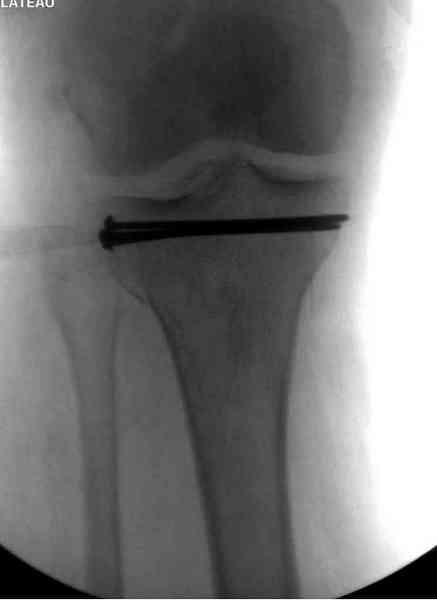

Снимки до и после закрытой репозиции

Пациентки прооперирована, результат чего на снимках. Выполнена открытая репозиция костей правой голени, синтез малоберцевой пластиной, б/берцевой винтами, имеющиеся фиксаторы не подходили, было принято решение репонировать отломки, синтез винтами, гипсовая повязка.

Мыщелок левой б/б кости репонирован закрыто, на контрольной рентгенограмме репозиция удовлетворительная, фиксировано спицами. гипсовая повязка.

Репозиция внутрисуставных переломов неудовлетворительная и не адекватна.

В лечении переломов пилона восстановление длины малоберцовой является индикатором и ориентиром для успешного лечения. Первый этап восстановления по длине не удался, малоберцовая остается короткой, и репозиция суставной поверхности осталась неудовлетворительной. Длина передней колонны не восстановлена, а в дистальном фрагменте имеется флексия. Оставлена без внимания потеря кости в метафизе. Шурупы 4.5 мм будут выступать после спадения отека, и возможно будут причиной мягкотканого осложнения в гипсе.